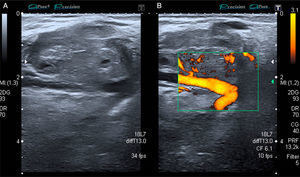

The patient was a 53-year-old man with no significant medical history. He presented with a painless mass in anterior forearm, reporting no previous injury. Physical examination confirmed the presence of a hard, immobile mass measuring less than 1cm. He came to the rheumatologic examination room, where he underwent soft tissue ultrasound (Toshiba Aplio®300). A round mass measuring less than 1cm was observed. It was iso/hypoechoic on gray scale images, was moderately well-defined, and was joined to a vessel that fed it (Fig. 1). On color Doppler, there was high echo intensity throughout the entire lesion, more intense on the periphery (Figs. 2 and 3). As there were findings that raised suspicion, such as heterogeneity, the marked vascularity and the marked Doppler signal (grade 3), magnetic resonance imaging was performed. This study revealed a round, well-defined form measuring 1cm, with hyperintensity on T1-weighted images, which pointed to a metastatic lesion (Fig. 4).